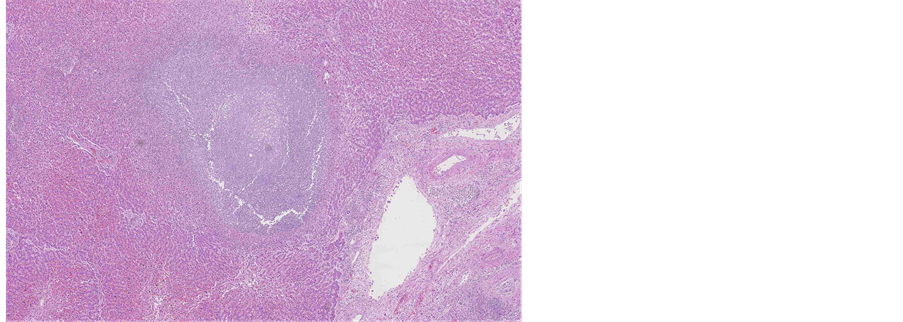

Histological evaluation of all specimens, removed from cervical cavity and obtained by biopsy revealed epithelial solid fields and cribriform areas of cells with enlarged nuclei and prominent nucleoli, atypical mitoses, partly eosinophilic and mostly significantly clear cytoplasm. Clear cell component was seen in 50% - 70% of the tumour (Figure 2).

Figure 2. Microscopic appearance of the endometrial tissue from curetting specimen-clear cell carcinoma, hematoxilin and eosin (H&E) staining, ×10.